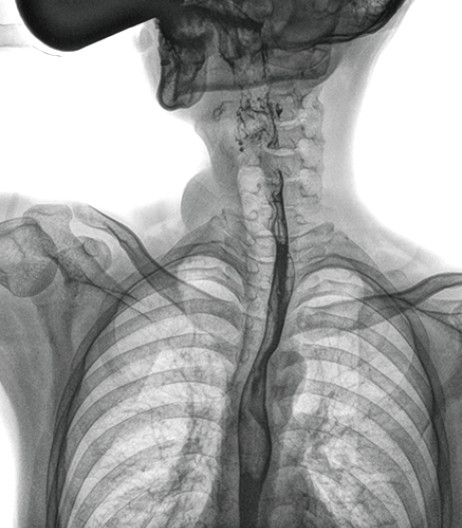

食管造影是食管病变的基本检查方法,可以发现食管癌的特征性改变——食管粘膜的中断和破坏,病人常感觉吞咽障碍,此特征在临床中最常见,也是早期食管癌的典型表现。一般伴随的特征有管壁充盈缺损、龛影、软组织块影、食管腔狭窄等;在透视下还可看到食管壁僵硬、蠕动缓慢等。

动态DR能够实现大幅面透视,瞬时高清点片等。在食管造影检查中,由于吞咽钡剂后,造影剂流速非常快,在一个大幅面上方便观察食管的病变。瞬时点片,可以实时捕捉到病变部位的影像,从而可以快速做出诊断。普利德多功能动态DR拥有17×17英寸超大视野,一次曝光即可显示整个食管,更方便观察食管的病变,确定病变的范围,对诊断和治疗有重要参考价值。

动态DR可以动态观察管壁蠕动是否僵硬,以鉴别良、恶性狭窄,不但在透视过程中,可实时高清点片,实现毫秒级动静态图像切换,快速捕捉病变部位的影像,成像清晰而迅速,尽可能减少食管功能性障碍患者因吞咽困难而忍受痛苦的时间,同时提高医生做出正确诊断的效率,还能实时保存视频影像,反复观察、分析,明确病变范围,对手术有重要的指导意义。

与过去的数字胃肠机比较,动态DR图像分辨率高,对食管的全景观察,局部粘膜破坏、中断,管腔狭窄以及病灶范围的显示清晰度明显更优。